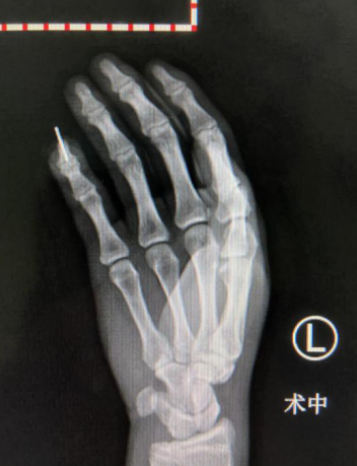

手外三医疗团队立即准备进行左小指修复术。术中拆除伤口缝线,彻底清除污染、失活组织;手法复位小指远节指骨骨折断端,克氏针固定。在高倍显微镜下,找到血管和神经断端,使用显微线吻合。少年手指远节的血管非常细,管腔直径仅0.5毫米,必须运用超级显微外科技术,在高倍显微镜下,保证一次性吻接成功。

术中